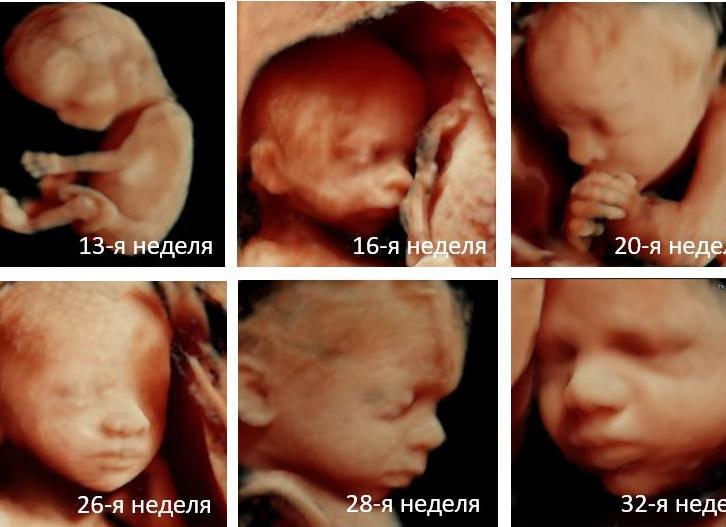

в общем у меня срок 5 акушерских недель и 3-4 дня или 3 недели и 3,4 дня дня от зачатия. по узи плодное яйцо неправилтьной формы 9*4,5 мм. врач сказала, что это очень мало, должно 17 мм. см. не исключила неразвивающуюся беременность, сказала через неделю повтор узи. в интернете таблицы, в идеале должно быть 18 мм на этом сроке и эмбрион 3 мм, но по одной таблице нашла, что 9 мм. соответствует сроку 5 недель и 5 дней. хгч у нас делают раз в неделю, завтра поеду сдам, но в динамике посмотреть не получится. у кого-нибудь было такое? может ли плодное яйцо отставать в развитии, но нормально развиваться?